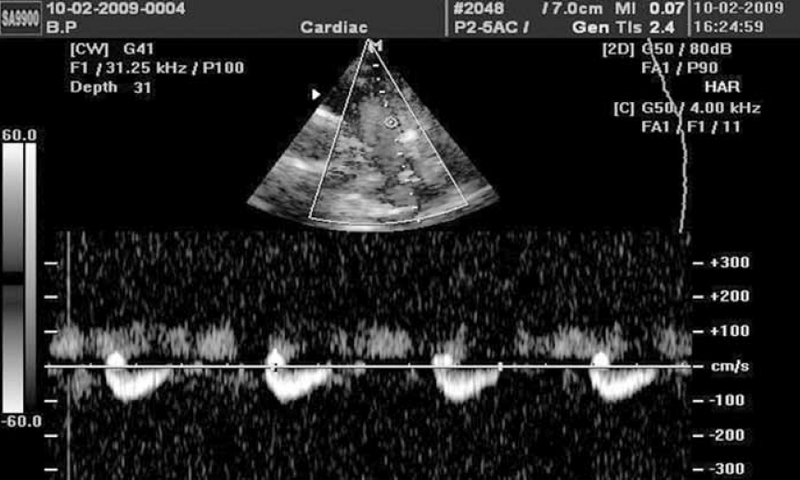

Восемь детей с наличием перекрестного сброса через ОАП в 100 % случаев наших наблюдений являлись недоношенными и имели повышенное давление в легочной артерии за счет бронхолегочной дисплазии (БЛД). ОАП в «стадии закрытия» диагностировался у детей 1-го года жизни старше 4 недель после периода новорожденности. При допплерографии ствола легочной артерии регистрируются волнообразные эпизоды практически полного отсутствия сброса через ОАП, сменяющиеся периодами нарастания сброса, сопровождающиеся появлением классической аускультативной картины (рис. 1).

Рис. 1. Допплерография ствола легочной артерии. Запечатлен эпизод значительного возрастания сброса через открытый артериальный проток, сопровождавшийся появлением систоло-диастолического шума

Диастолический сброс крови через коронарную фистулу в легочную артерию при постоянно-волновом допплеровском картировании отчасти напоминает аналогичный сброс через ОАП, однако является более низкоскоростным и менее продолжительным по времени, не занимая весь диастолический промежуток на допплерограмме (см. рис. 6).

Рис. 6. Диастолические потоки, отражающие сбросы крови через коронарную фистулу в ствол легочной артерии, визуализируются в секторе положительных значений над изолинией между систолическими и могут симулировать допплерограмму при классическом открытом артериальном протоке